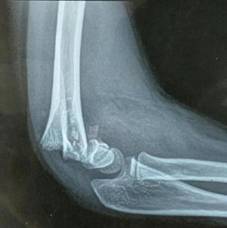

微创治疗肱骨干骨折

优点:闭合复位,不干扰骨折断端,中心固定,利于愈合。